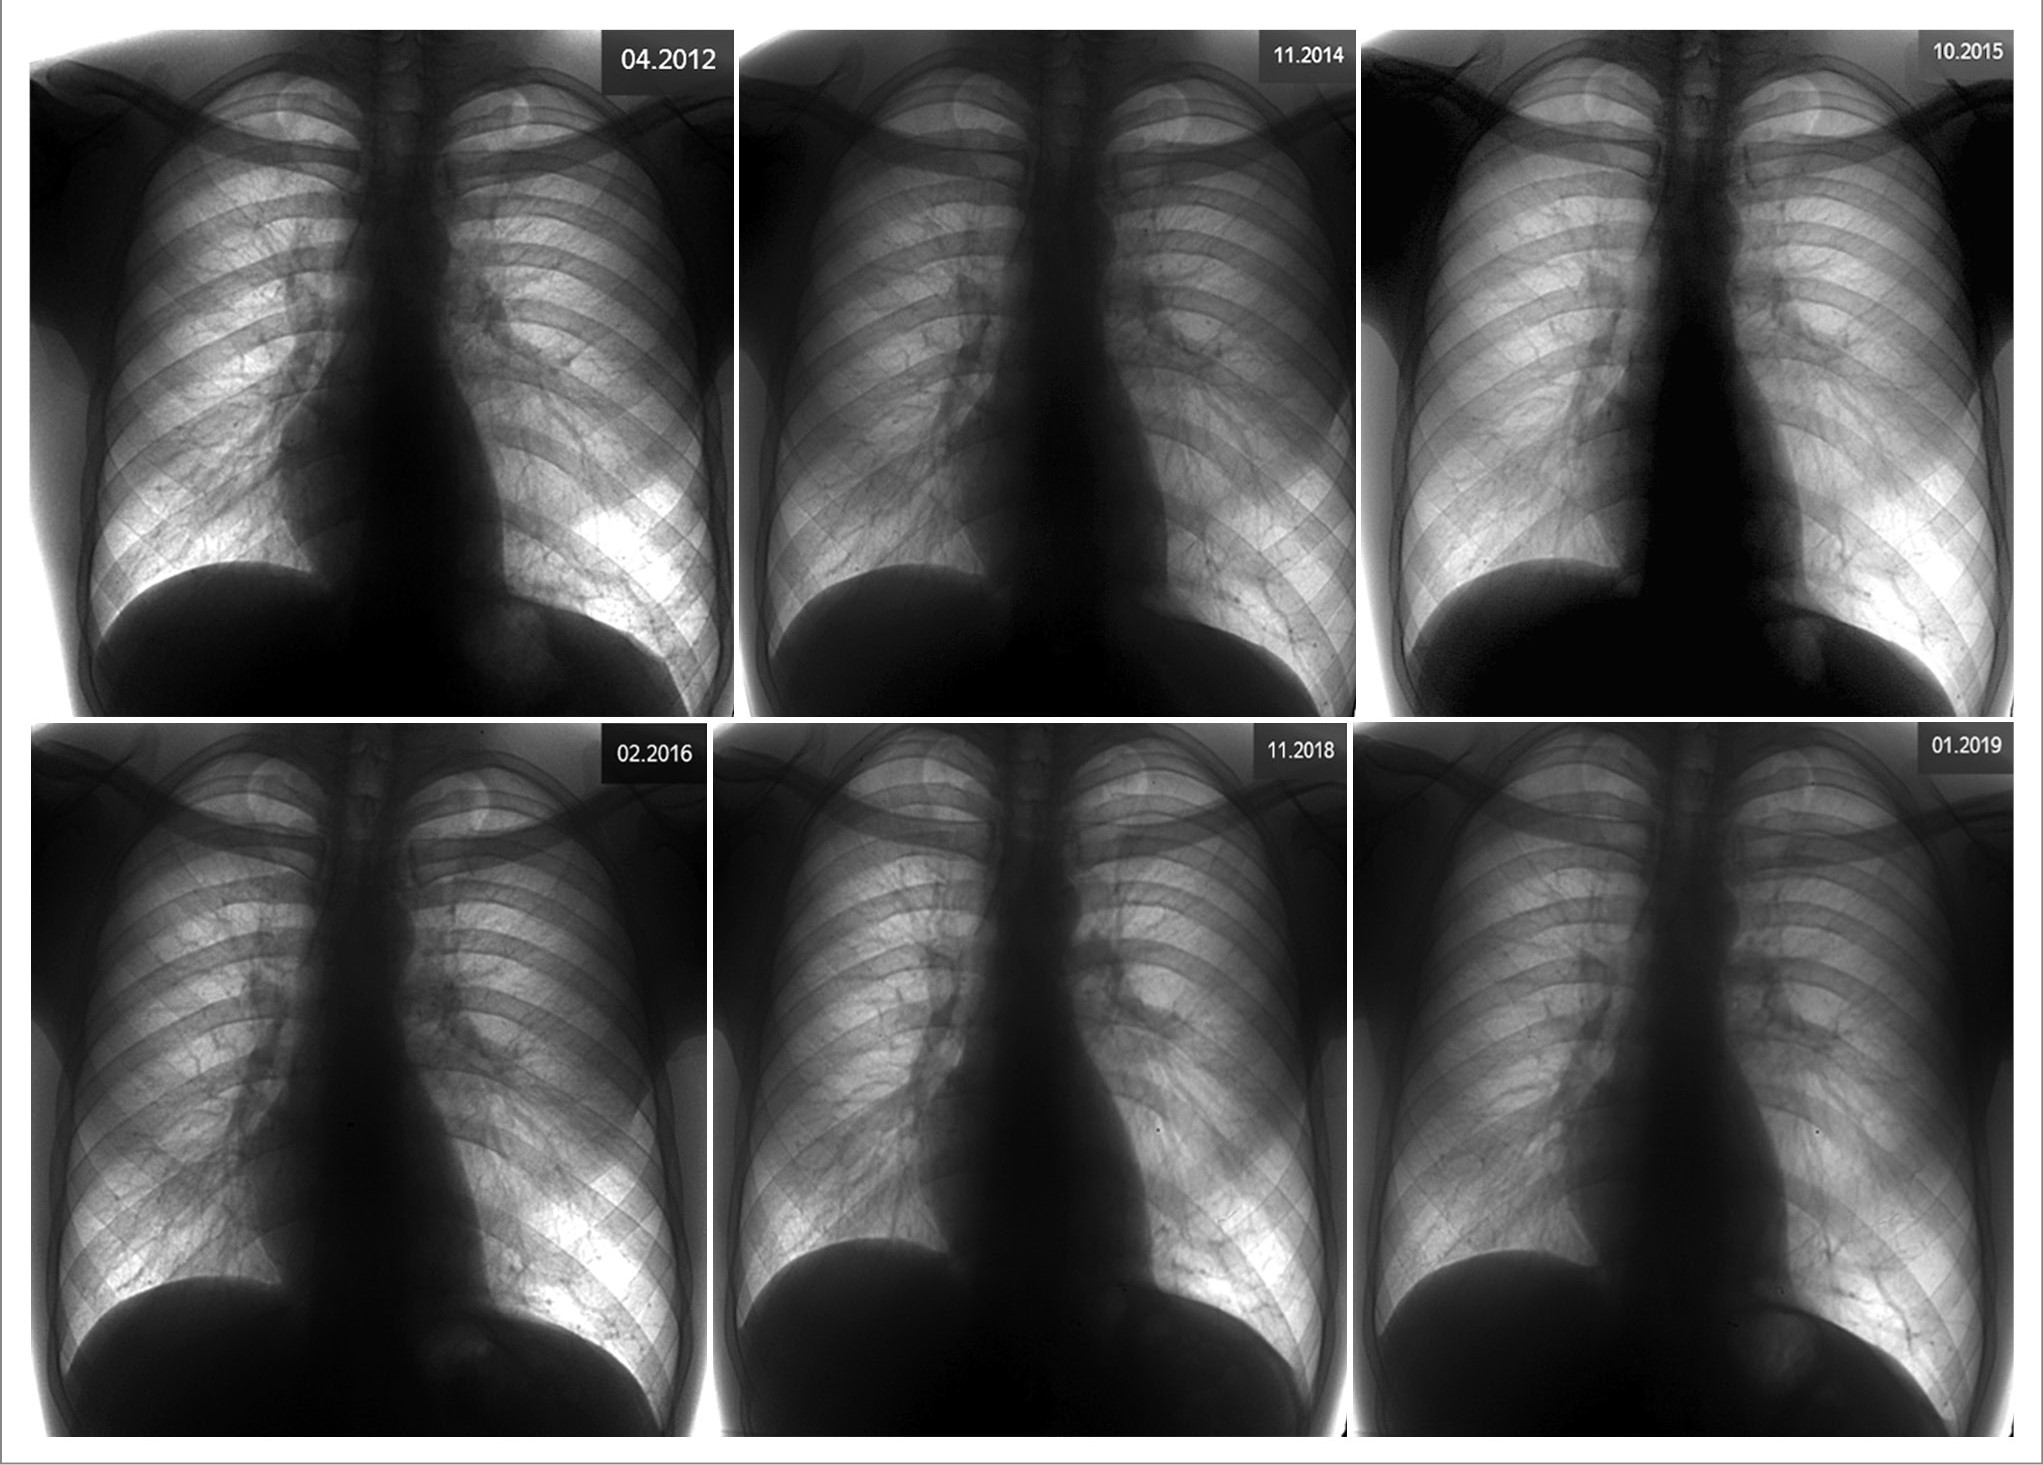

На представленной рентгенограмме ОГК, выполненной на предыдущем этапе лечения в ноябре 2023 г., инфильтративных изменений легочной ткани не выявлено. Левое легкое визуально больше в объеме. Отмечается участок повышенной воздушности легочной ткани в базальных отделах слева за счет измененного (обедненного) сосудистого рисунка (по сравнению с правыми отделами), смещение тени сердца вправо (рис. 1).

Рис. 1. Рентгенограмма ОГК в двух проекциях.

Определяется: a – левое легкое больше в объеме, участок ограниченного просветления легочной ткани в базальных отделах слева за счет повышенной воздушности легочной ткани (по сравнению с правыми отделами), смещение тени сердца вправо, купол диафрагмы слева косонисходящий; b – на уровне тела Th11 позвонка визуализируются 3 округлых участка высокой плотности с четкими ровными контурами – ортогонально расположенные сосуды.

Важно подчеркнуть, что ретроспективный анализ рентгенологического архива пациента с 2012 г., клинической картины и результатов МСКТ от ноября 2023 г. вызывал серьезное сомнение в «односторонней левосторонней эмфиземе легкого с бронхоэктазами» или тем более в «пневмоническом» характере изменений.

Очевидно, что врачами-рентгенологами и клиницистами с момента наблюдения за пациентом неверно интерпретировались указанные изменения в легких. Имеющиеся описания рентгенографии ОГК при диспансерном наблюдении как «вариант нормы» не отвечали как минимум на три важных вопроса. Почему при каждом исследовании имеются смещение средостения вправо, нарушение архитектоники бронхиального дерева слева (высокое отхождение нижнедолевого бронха) и наличие гиперпрозрачного левого легкого в проекции нижней доли? Мы приводим в качестве примера рентгенологические исследования пациента в динамике (рис. 5).

Рис. 5. Рентгенограммы ОГК в прямой проекции 2012–2019 гг.

На снимках определяется: левое легкое больше в объеме, участок просветления легочной ткани в базальных отделах слева за счет повышенной воздушности легочной ткани (по сравнению с правыми отделами), смещение тени сердца вправо.